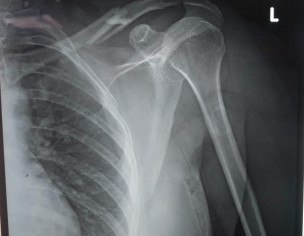

My wife has suffered an accident and fractured her left clavicle. The ortho specialist said there will be no intervention, and just put a tight 8 bandage around her shoulder and instructed it to get rebandaged twice a week to make sure it remains tight. 6 weeks recovery time has been suggested. X-rays are being attached for reference. Please advice if what has been suggested is appropriate or something more needs to be done?

Thnx for opinion,there are 2 xray films,no date of exposure is mentioned on them,in both xray films,there is difference in fracture ever most of clavicle fractures r managed non operatively,so is this one u said,tight 8 bandage,this is not tight but figure 8 bandage.4 weeks r sufficient to put this fracture in such u have consulted orthopaedic surgeon,then u must follow periodically as he advised y u felt the need of 2nd opinion?

Dr. Dileep Kumaar: The X-rays were taken an hour after the accident took place. Both X-rays at the same time, but with different position of the hand... Need for 2nd opinion arose because someone told me that the figure 8 bandage is not needed in cases like these.